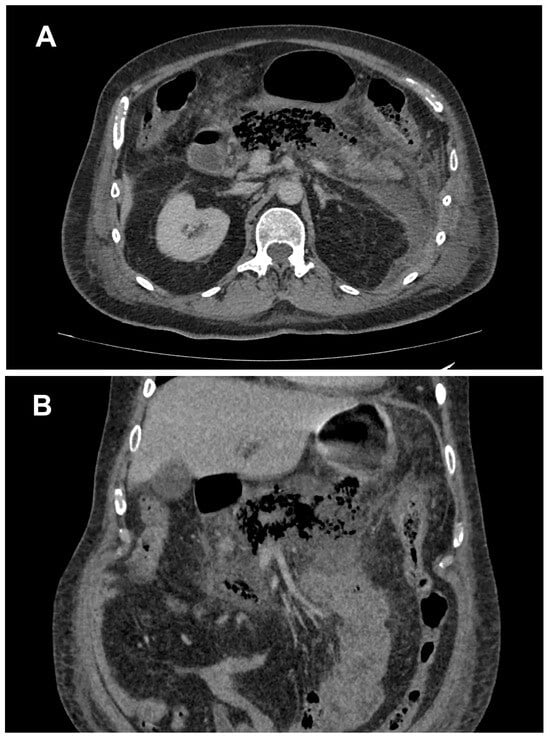

2. Case Presentation